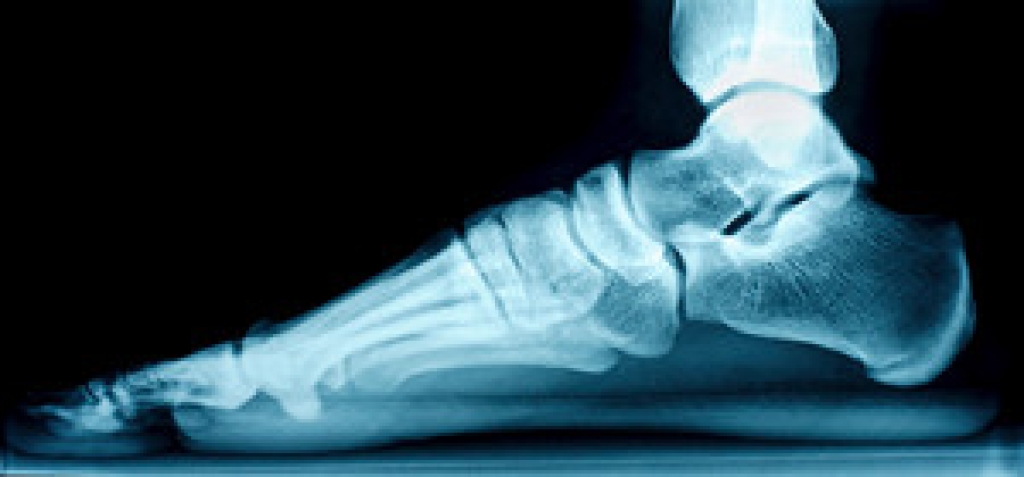

Foot fractures in adults are injuries that can occur from trauma such as falls, car accidents, or even overuse. Signs and symptoms of a foot fracture include immediate pain, swelling, bruising, and difficulty bearing weight on the affected foot. In some cases, there may be visible deformity or an inability to move the toes. Diagnosis typically involves a physical examination and imaging studies like X-rays or CT scans to determine the exact location and extent of the fracture. Treatment depends on the severity of the fracture, as minor fractures may be treated with rest, compression, and elevation, along with immobilization using a cast or brace. More severe fractures may require surgery to realign and stabilize the bones with plates or screws. Healing times vary depending on the type of fracture and treatment, but generally, it takes several weeks to months. If you have sustained a foot fracture, it is suggested that you consult a podiatrist for treatment.

Broken Foot Causes, Symptoms, and Treatment

A broken foot is caused by one of the bones in the foot typically breaking when bended, crushed, or stretched beyond its natural capabilities. Usually the location of the fracture indicates how the break occurred, whether it was through an object, fall, or any other type of injury.

Treatment for broken bones varies depending on the cause, severity and location. Some will require the use of splints, casts or crutches while others could even involve surgery to repair the broken bones. Personal care includes the use of ice and keeping the foot stabilized and elevated.